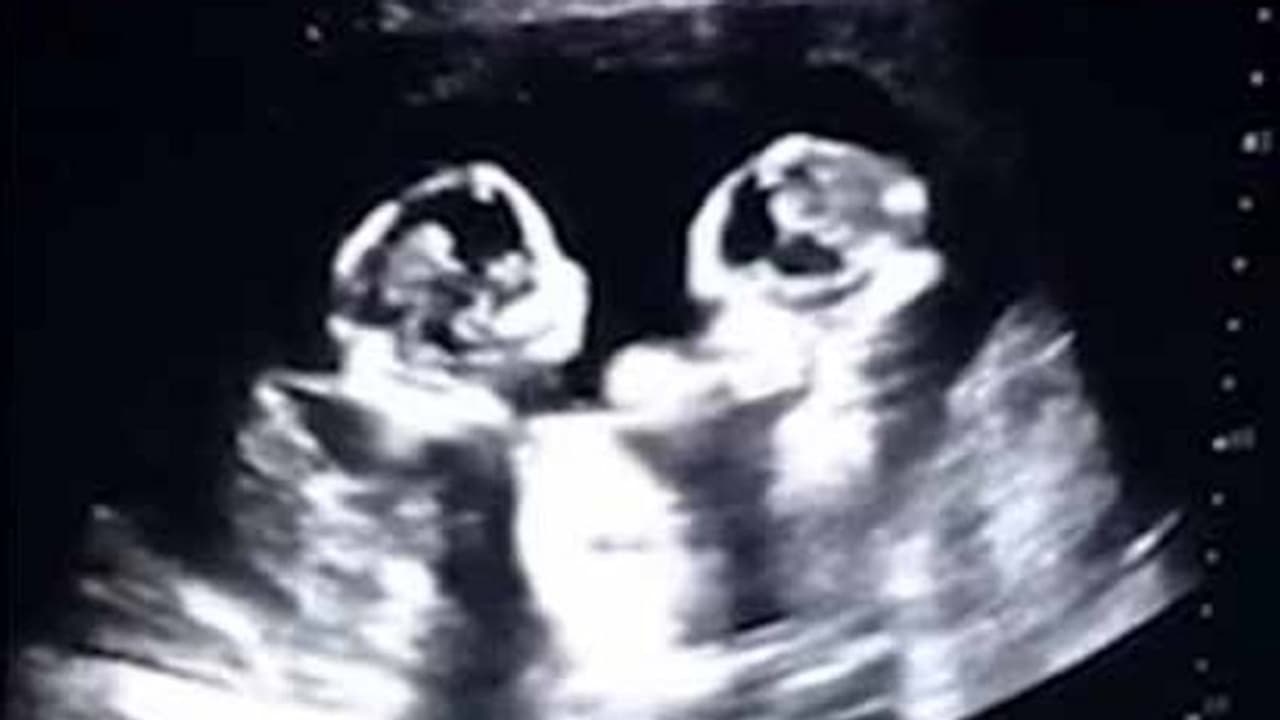

சீனாவை சேர்ந்த 28 வயதான தாவோ என்பவர் அவருடைய கர்ப்பிணி மனைவியை அருகில் உள்ள மருத்துவமனையில் சிகிச்சைக்காக சேர்த்துள்ளார். அப்போது ஸ்கேன் செய்தபோது கர்ப்பிணியின் வயிற்றில் இருந்த இரட்டை குழந்தைகள் ஒன்றுக்கொன்று சண்டையிடும் அழகிய காட்சியை கண்டுள்ளனர். உடனடியாக தன்னுடைய மொபைல் போனை எடுத்து வீடியோவாக பதிவு செய்த அவர் தற்போது அந்த வீடியோவை சமூக வலைத் தளத்தில் பதிவிட்டு மகிழ்ந்து உள்ளார்.

இந்த வீடியோவை பார்த்த சமூகவலைத்தள வாசிகள் பல்வேறு கருத்துக்களை பகிர்ந்து வருகின்றனர். இந்த வீடியோ மட்டும் இதுவரை இரண்டரை மில்லியன் பார்வையாளர்களை கடந்து உள்ளது என்பது குறிப்பிடத்தக்கது. தற்போது பிறந்துள்ள இந்த குழந்தைகளுக்கு செர்ரி மற்றும் ஸ்ட்ராபெர்ரி என பெயரிட்டு அழைத்து வருகின்றனர் பெற்றோர்கள்.